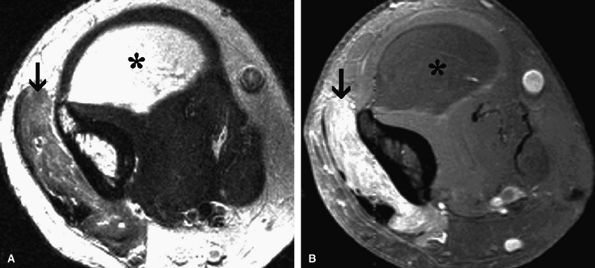

FIGURE 12.9 ● Quadrilateral space syndrome. Axial (A) and oblique coronal (B) PD-weighted images demonstrate selective atrophy and fatty infiltration of the teres minor muscle (asterisk).

|